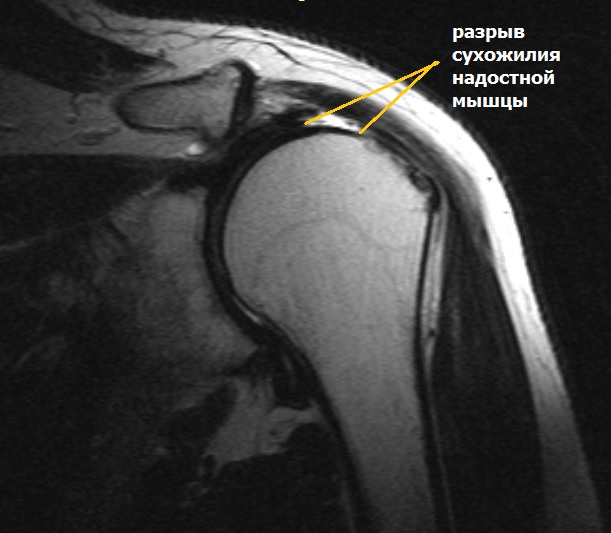

Повреждение мышц мрт

Повреждение мышц мрт 88 фото